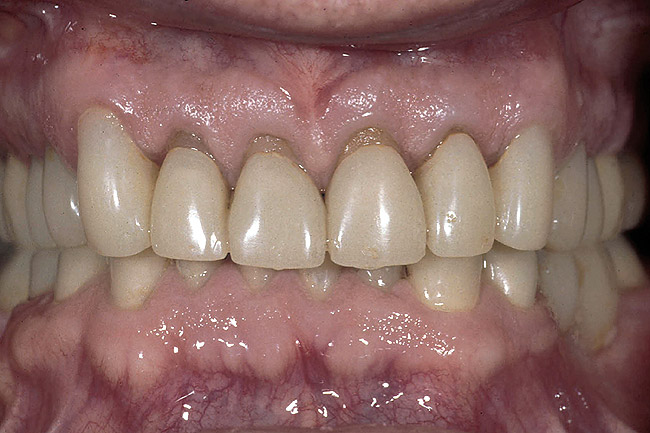

Figure 10  The final restorations demonstrate the esthetic and functional changes from lengthening the incisal edges and raising the gingiva.

Figure 10